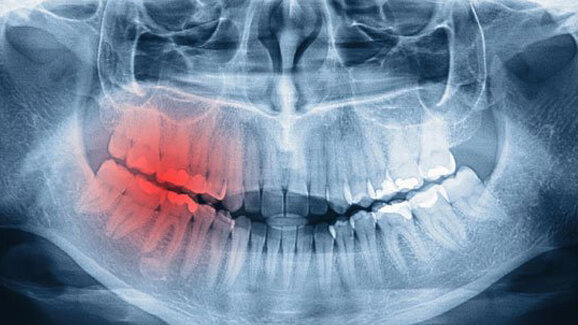

Bei der Rekonstruktion erschaffen die Chirurgen zwar nicht aus einer Rippe eine Frau, aber mit trickreichen lokalen Lappentechniken und mikrochirurgischen Composite Lappen sind sie in der Lage zumindest große Gesichtsanteile dreidimensional anatomisch und funktionell zu rekonstruieren. Im Vergleich dazu könnte die Implantologie fast banal erscheinen. Wenn man jedoch die modernen Techniken des „backward planning“ mit Navigation oder Schablonenführung, minimalinvasive Augmentationstechniken (Schalungstechnik, hydraulische Sinuslifttechniken) und das ausgefeilte Weichgewebsmanagement betrachtet erkennt man, dass eine eigene Wissenschaft entstanden ist. Nur wer in der Lage ist auch dieses Feld auf höchstem Niveau abzudecken, wird hier weiter bestehen können.